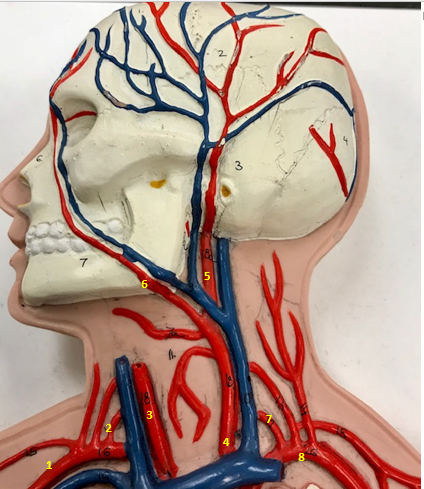

Right subclavian artery

Name #1

Supplies blood to right arm and shoulder

Function of right subclavian artery (1)

Right vertebral artery

Name #2

Supplies blood to brain and spinal cord

Function of right vertebral artery (2)

Right common carotid artery

Name #3

Supplies blood to right neck and head

Function of right common carotid artery (3)

Left common carotid artery

Name #4

Supplies blood to left neck and head

Function of left common carotid artery (4)

Left external carotid artery

Name #5

Supplies blood to face neck and skull

Function left external carotid artery (5)

Left facial artery

Name #6

Supplies blood to face and neck

Function of left facial artery (6)

Left vertebral artery

Name #7

Supplies blood to brain and spinal cord

Function of left vertebral artery (7)

Left subclavian artery

Name #8

Supplies blood to left arm and shoulder

Function of left subclavian artery (8)